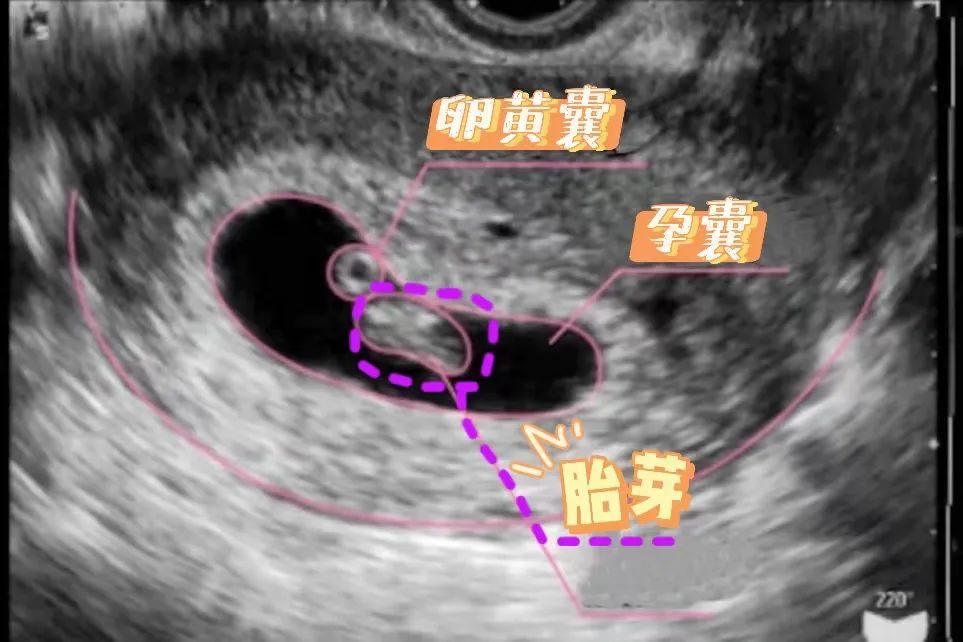

第4周末,在B超检查下,已经可以见到7毫米大小的孕囊了,并且每天以1毫米的速度生长。

不过每个小人儿发育情况不同,有些人可能要到怀孕第5周才能看到。